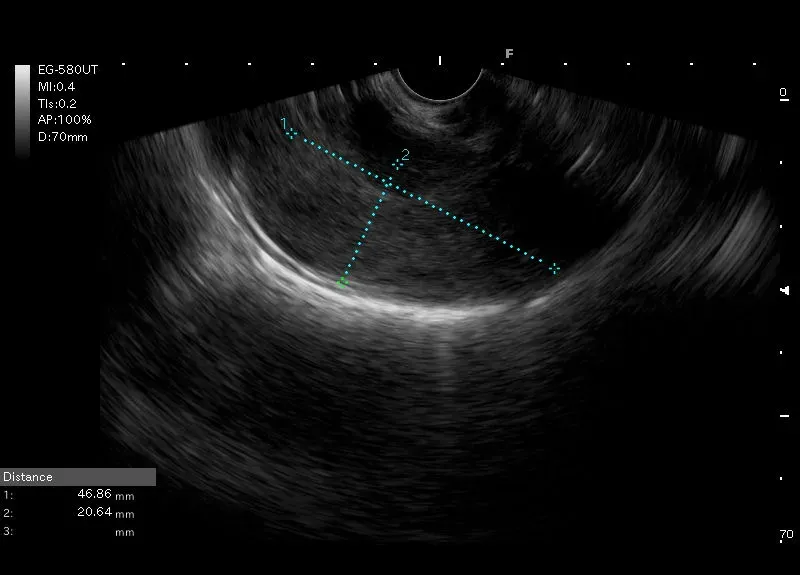

Zmiana lita wielkości 47/43 mm o gładkich brzegach, położona w pobliżu lewego płata wątroby, nie łącząca  się z wątrobą ani śledzioną i kontaktująca się ze ścianą żołądka.

Echogeniczność zmiany zbliżona do śledziony-   zmiana może odpowiadać śledzionie dodatkowej.